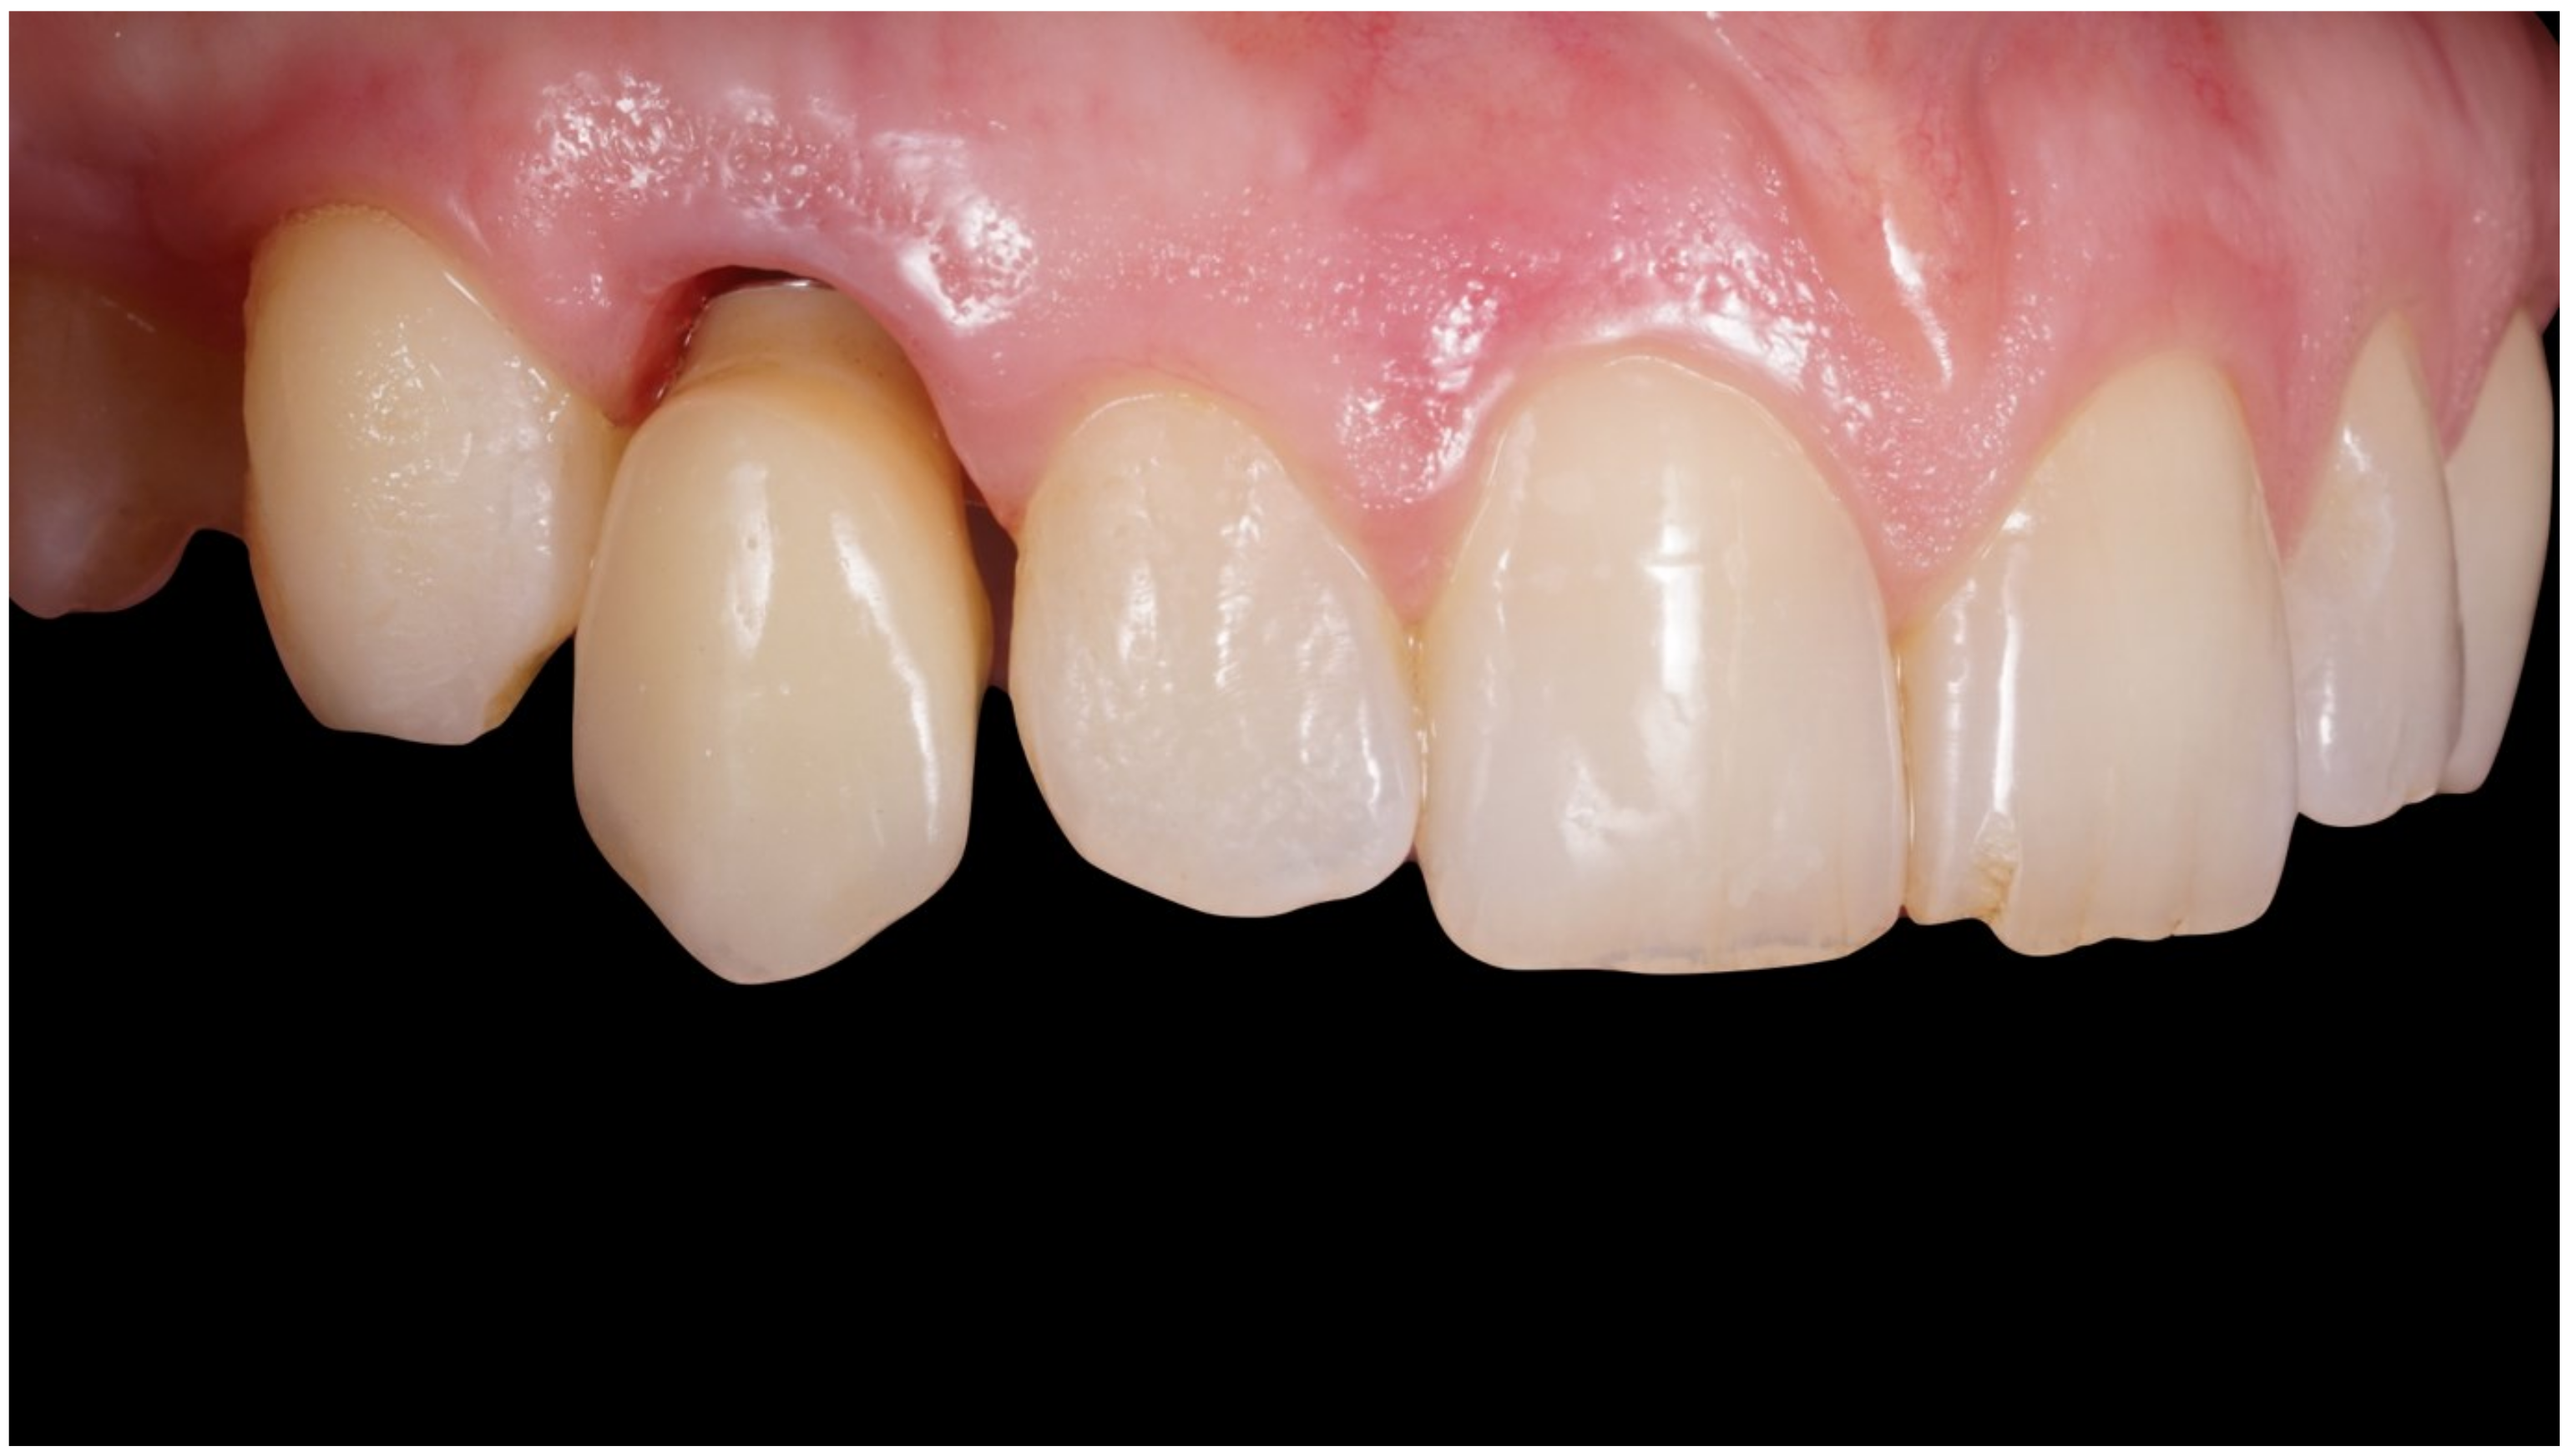

Figure 4.

Immediate temporization of immediately placed implant.

Figure 5.

Periapical X-ray at immediate temporization.